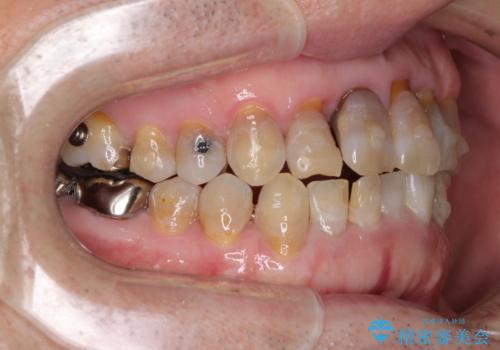

上顎の狭窄歯列 インビザラインによる拡大矯正

- 前歯の叢生と臼歯のクロスバイトを気にして来院された患者様です。

急速拡大装置による上顎の側方拡大を行い、その後はインビザラインより歯列を改善することとしました。

20代後半以降の男性は上顎骨の側方拡大処置の成功率が低く、今回も骨を拡大することができませんでした。

しかしながら、歯列を側方に拡大することができ、その後はインビザラインにて叢生を解消することができました。